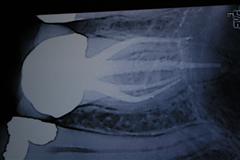

Rentgenska kontrola polnitve koreninskih kanalov.

Gospa je prišla na tretji obisk sproščena in zadovoljna in se ni pritoževala zaradi bolečin na dotičnem zobu. Zob smo ponovno odprli, počistili ostanke zdravilnega koreninskega vložka, ki smo ga vstavili v drugi fazi in osušili koreninske kanale. Pregleg koreninskih kanalov s pomočjo povečeval zmanjša verjetnost, da bi v kanalu pustili ostanke vložka. Zob smo ponovno slikali z digitalnim RTG aparatom in s pomočjo v kanale uvedenih srebrnih igel natančno določili dejansko dolžino le teh. Zob smo dokončno zapolnili z plastičnimi masami in dodatno s polnilno maso (AH 26), ki natačno zatesni kanale in zmanjša možnost za ponolni razvoj bakterij. Na koncu smo natančnost polnitve kontrolirali s ponovnim RTG posnetkom, ki je pokazal natančno in homogeno polnitev.

Rentgenska kontrola polnitve.